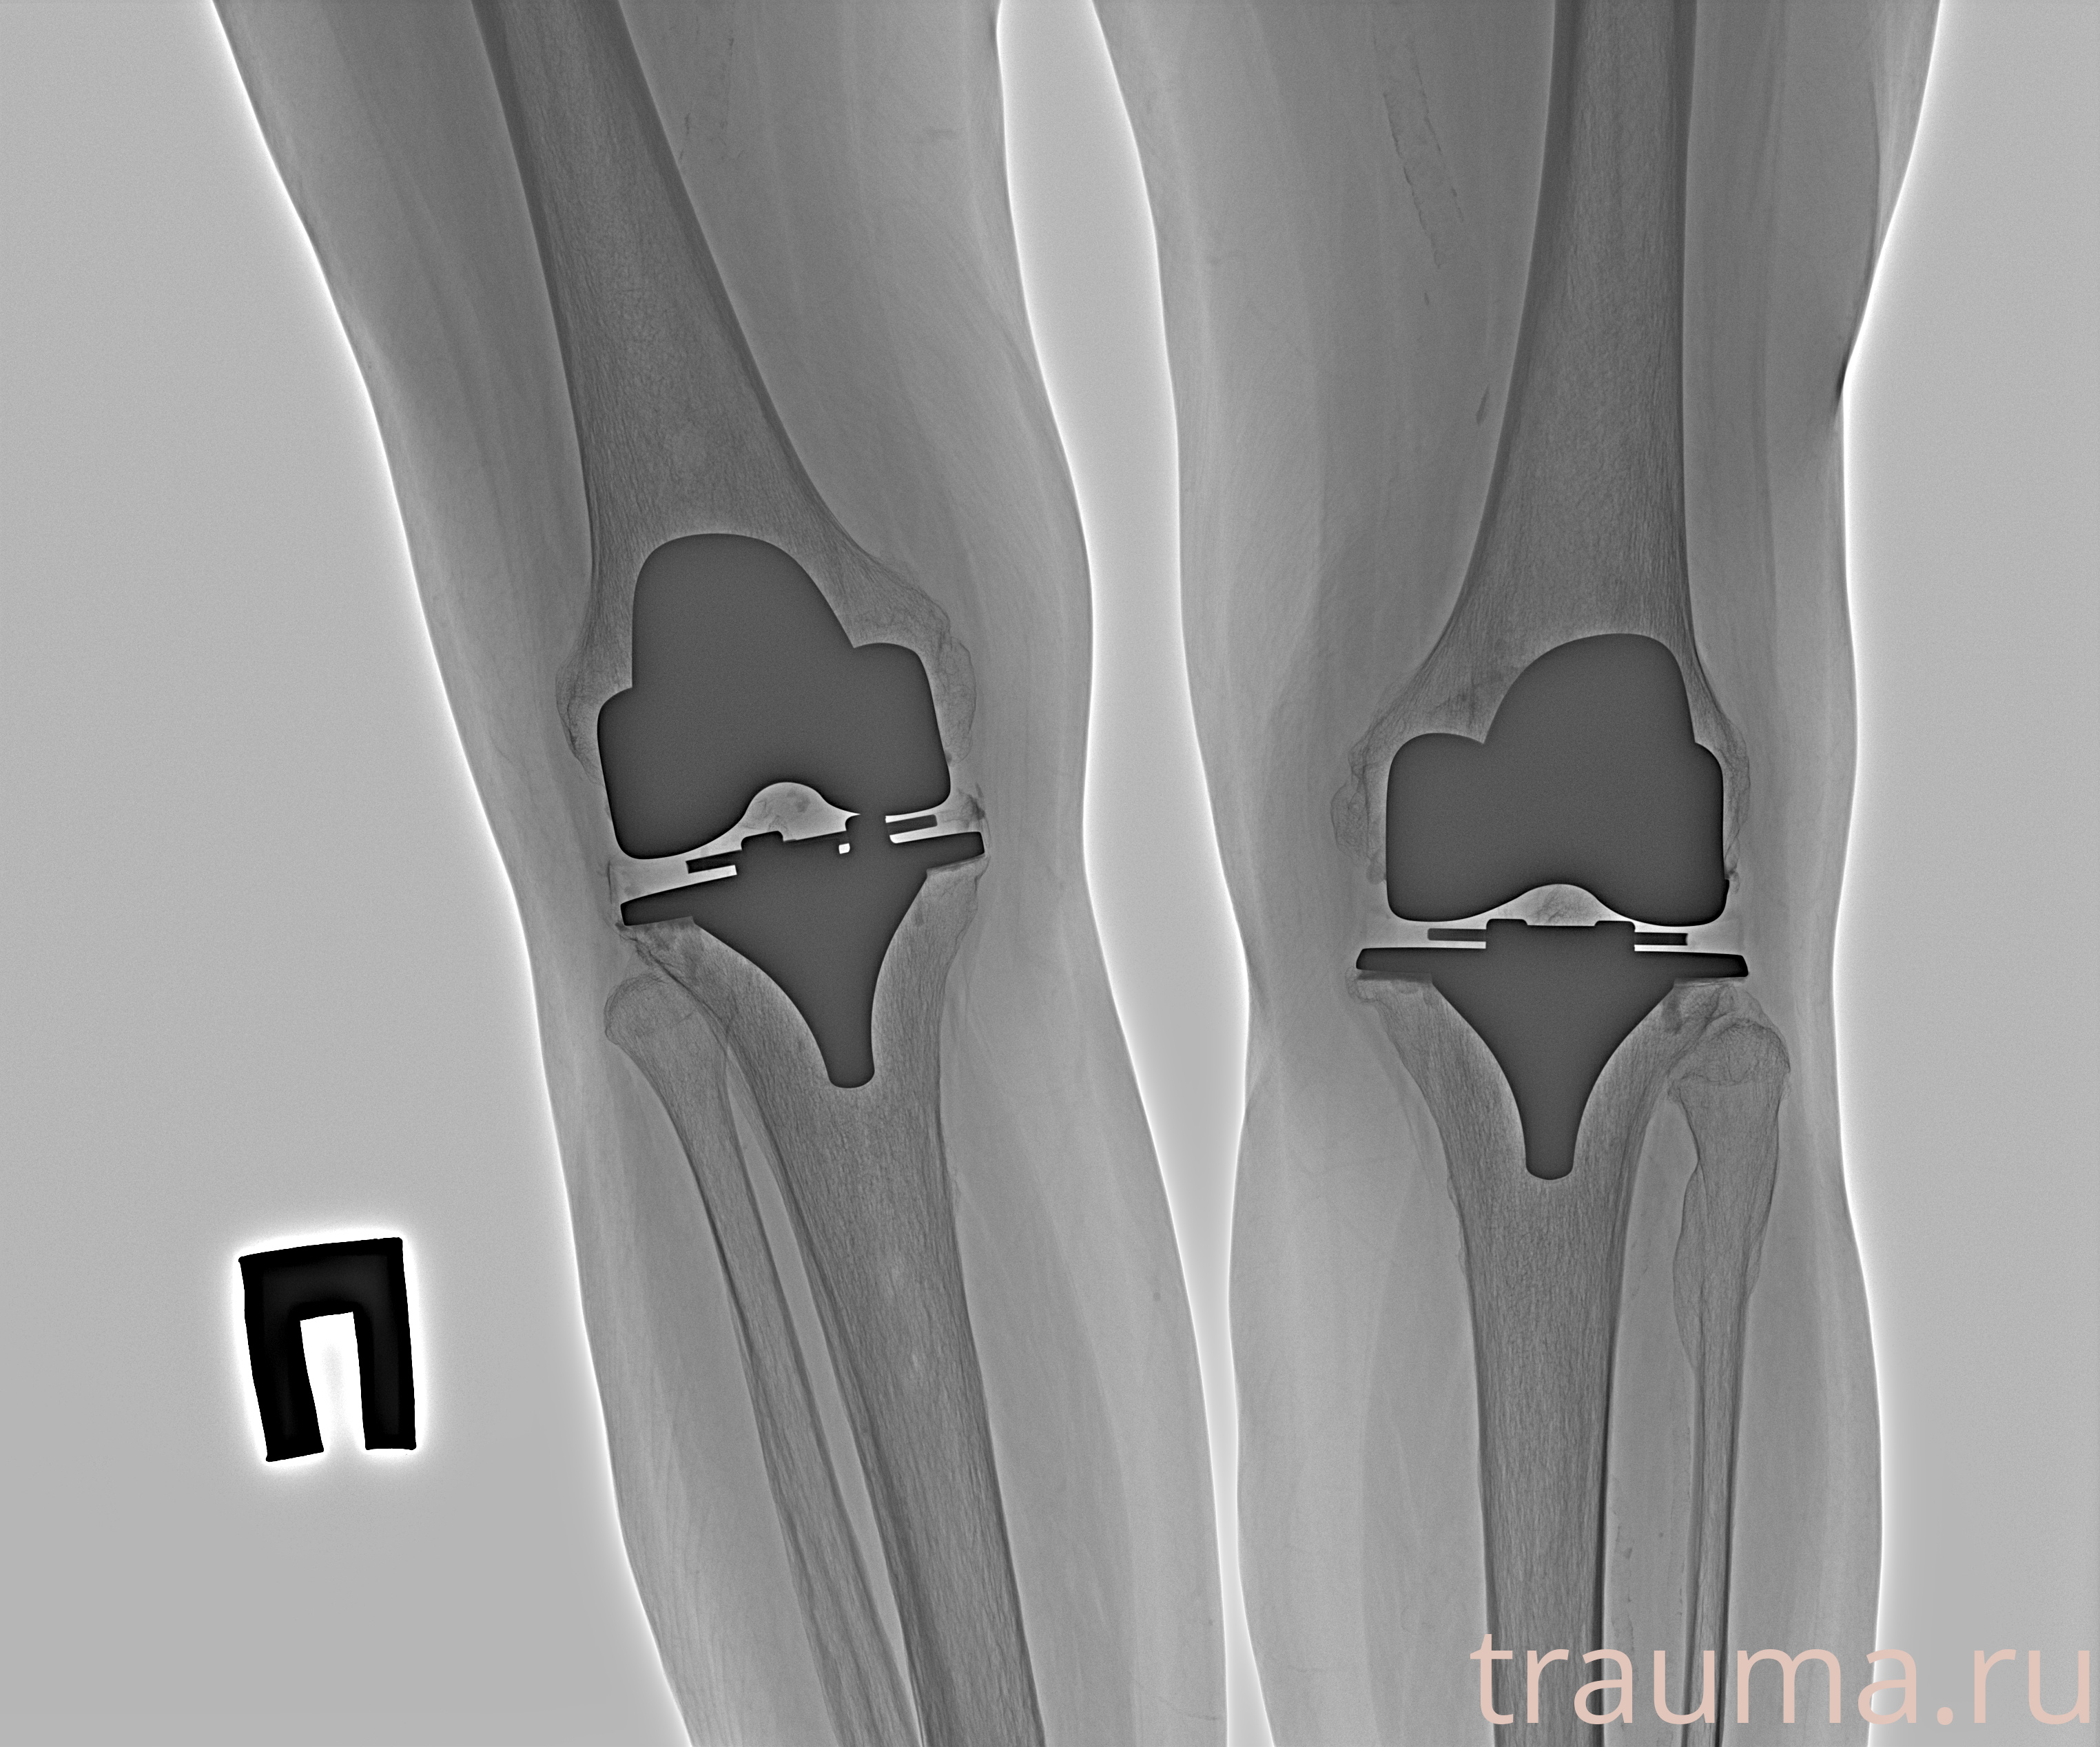

Рентгенограммы

Рентген на дому: по вашему адресу приезжает врач-рентгенолог, травматолог-ортопед с мобильным рентгеновским аппаратом, проводит диагностику травмы или заболевания, делает необходимые рентгенограммы, дает рекомендации по дальнейшему лечению. Получить качественные снимки в домашних условиях возможно благодаря уникальной методике, разработанной МосРентген Центром для института  Склифосовского